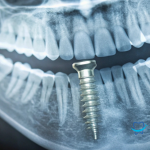

Así pasa igualmente con los tratamientos dentales. Algunos de ellos, dependiendo de su complejidad, pueden provocar manchas en las encías de manera temporal.

También contamos con varias promociones activas en técnicas de blanqueamiento, ortodoncias, implantes y prótesis. Acude a una de nuestras más de 1900 clínicas y comienza a cuidar tu sonrisa por tan sólo 54,45€ al año. ¡Hazte socio de Servibucal!